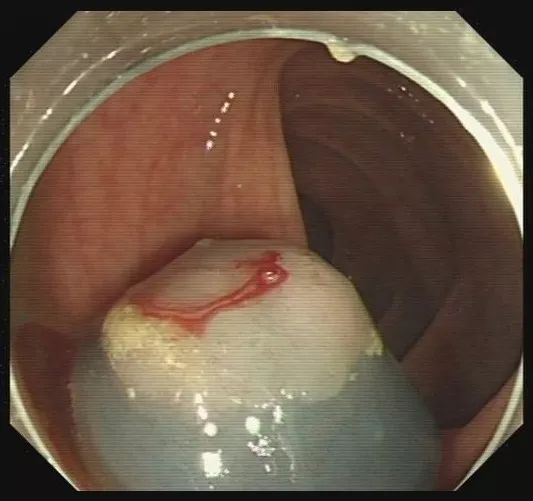

步骤四:轻轻向肠腔内提起息肉,使钢丝圈尽量远离肠壁黏膜。

图片

步骤五:在钢丝圈上脉冲式通高频电进行电灼烧,直至息肉根部被切断,息肉脱落。